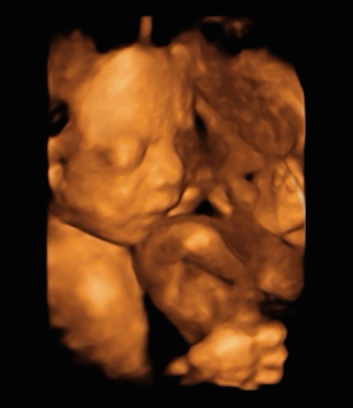

〖23 w〗脹氣、便秘、腸胃絞痛... 醫生建議我每天要喝足2,000 cc的水分。高層次超音波,確定寶寶性別,第一次看到4D的寶寶長相。想出第二個 中文 ideal baby name

寶寶很喜歡在媽咪肚子裡玩臍帶、喜歡用小手手遮住自己的臉(不喜歡看鏡頭)> //// <

當時我還問了超音波師:「是不是太亮了?」所以寶寶都不正面對我們,哈哈哈XDDD

( 醫師說媽咪的腹中是非常暗的喔,所以其實寶寶也看不到東西)

只能說小小的他很有自己的個性吧 ![]()

看到很多在寶寶周圍的小水泡,那就是氧水 感覺好可愛喔 <有點像是「不存在的世界」>